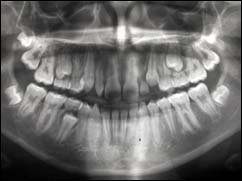

PANORAMIQUE :